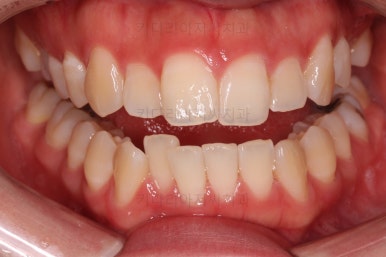

부산비대칭교정 마무리 때의 입안의 모습입니다.

가지런한 느낌은 좋지만 정중선 당연히 약간 안맞고요.

폭도 100%는 안맞아서 어금니쪽이 약간 애매한 교합이기도 했습니다.

하지만 이정도의 비대칭 상황에서 이정도의 교합은 교정만으로 할 수 있는 베스트가 아닌가 생각됩니다.

전후 비교 사진인데요.

입매가 비발치임에도 불구하고 매우 좋아졌고요.

치열과 교합도 매우 좋아졌습니다.